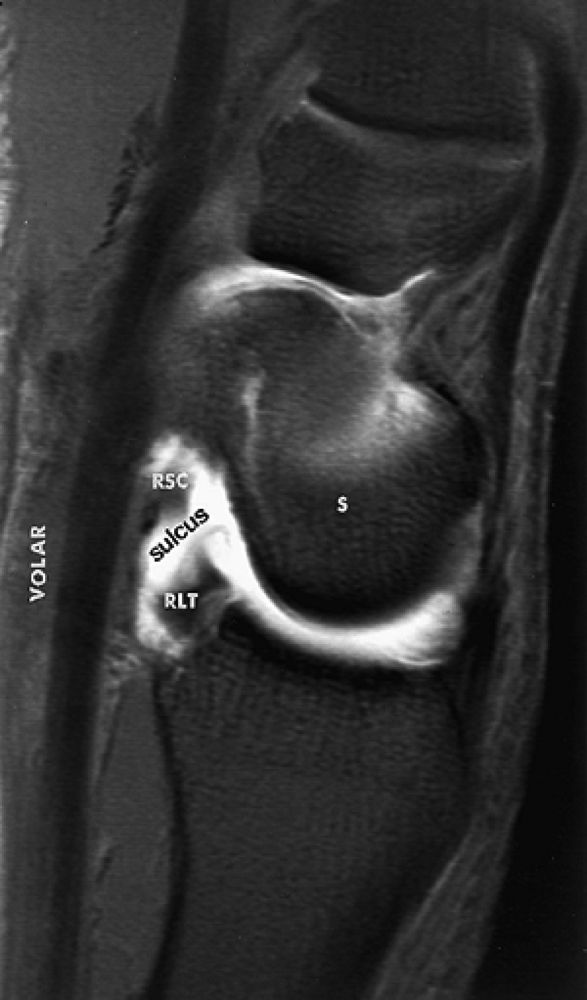

similar to the radioscaphocapitate ligament. There is an interligamentous sulcus between the radioscaphocapitate and the radiolunotriquetral ligaments on sagittal images (Fig. 10.65). The radiolunotriquetral is a strong ligament that stabilizes the proximal carpal row on the radius and should be differentiated from the radioscapholunate ligament.

FIGURE 10.65 ● The interligamentous sulcus between the radioscaphocapitate (RSC) and radiolunotriquetral ligaments is seen on an FS sagittal T1-weighted arthrogram at the level of the scaphoid (S). The volar aspect of the wrist is labeled. The radio-lunotriquetral ligament is proximal to the RSC ligament.

FIGURE 10.62 ● Anatomy of the radioscaphocapitate (RSC), radiolunotriquetral (RLT), and radioscapholunate (rsl) ligaments at the level of the distal volar radius (R). T, triquetrum; S, scaphoid. FS T1-weighted arthrogram after radiocarpal injection.